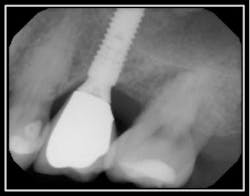

Radiographic Resorption:

Perioscopic view of external root resorption #15.Suggested Etiology: Impacted 3rd molar The below case identifies external root resorption which extends into the cementum and dentinal structures.

Pre-op radiograph #15

The above pictures identify the resorption. The interior of the resorption is quite hard and may be Reparative dentin, which is formed as a reaction to external stimulation.

Treatment for this type of defect may vary depending upon the extent of the resorption.